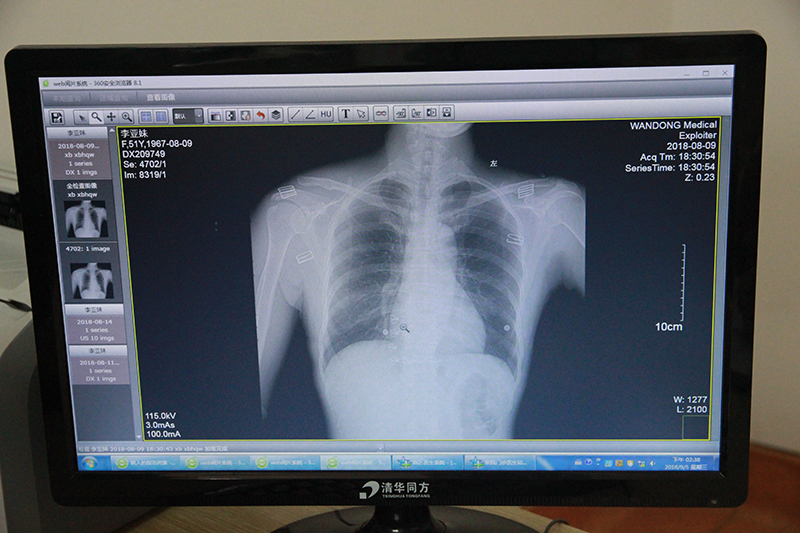

术前